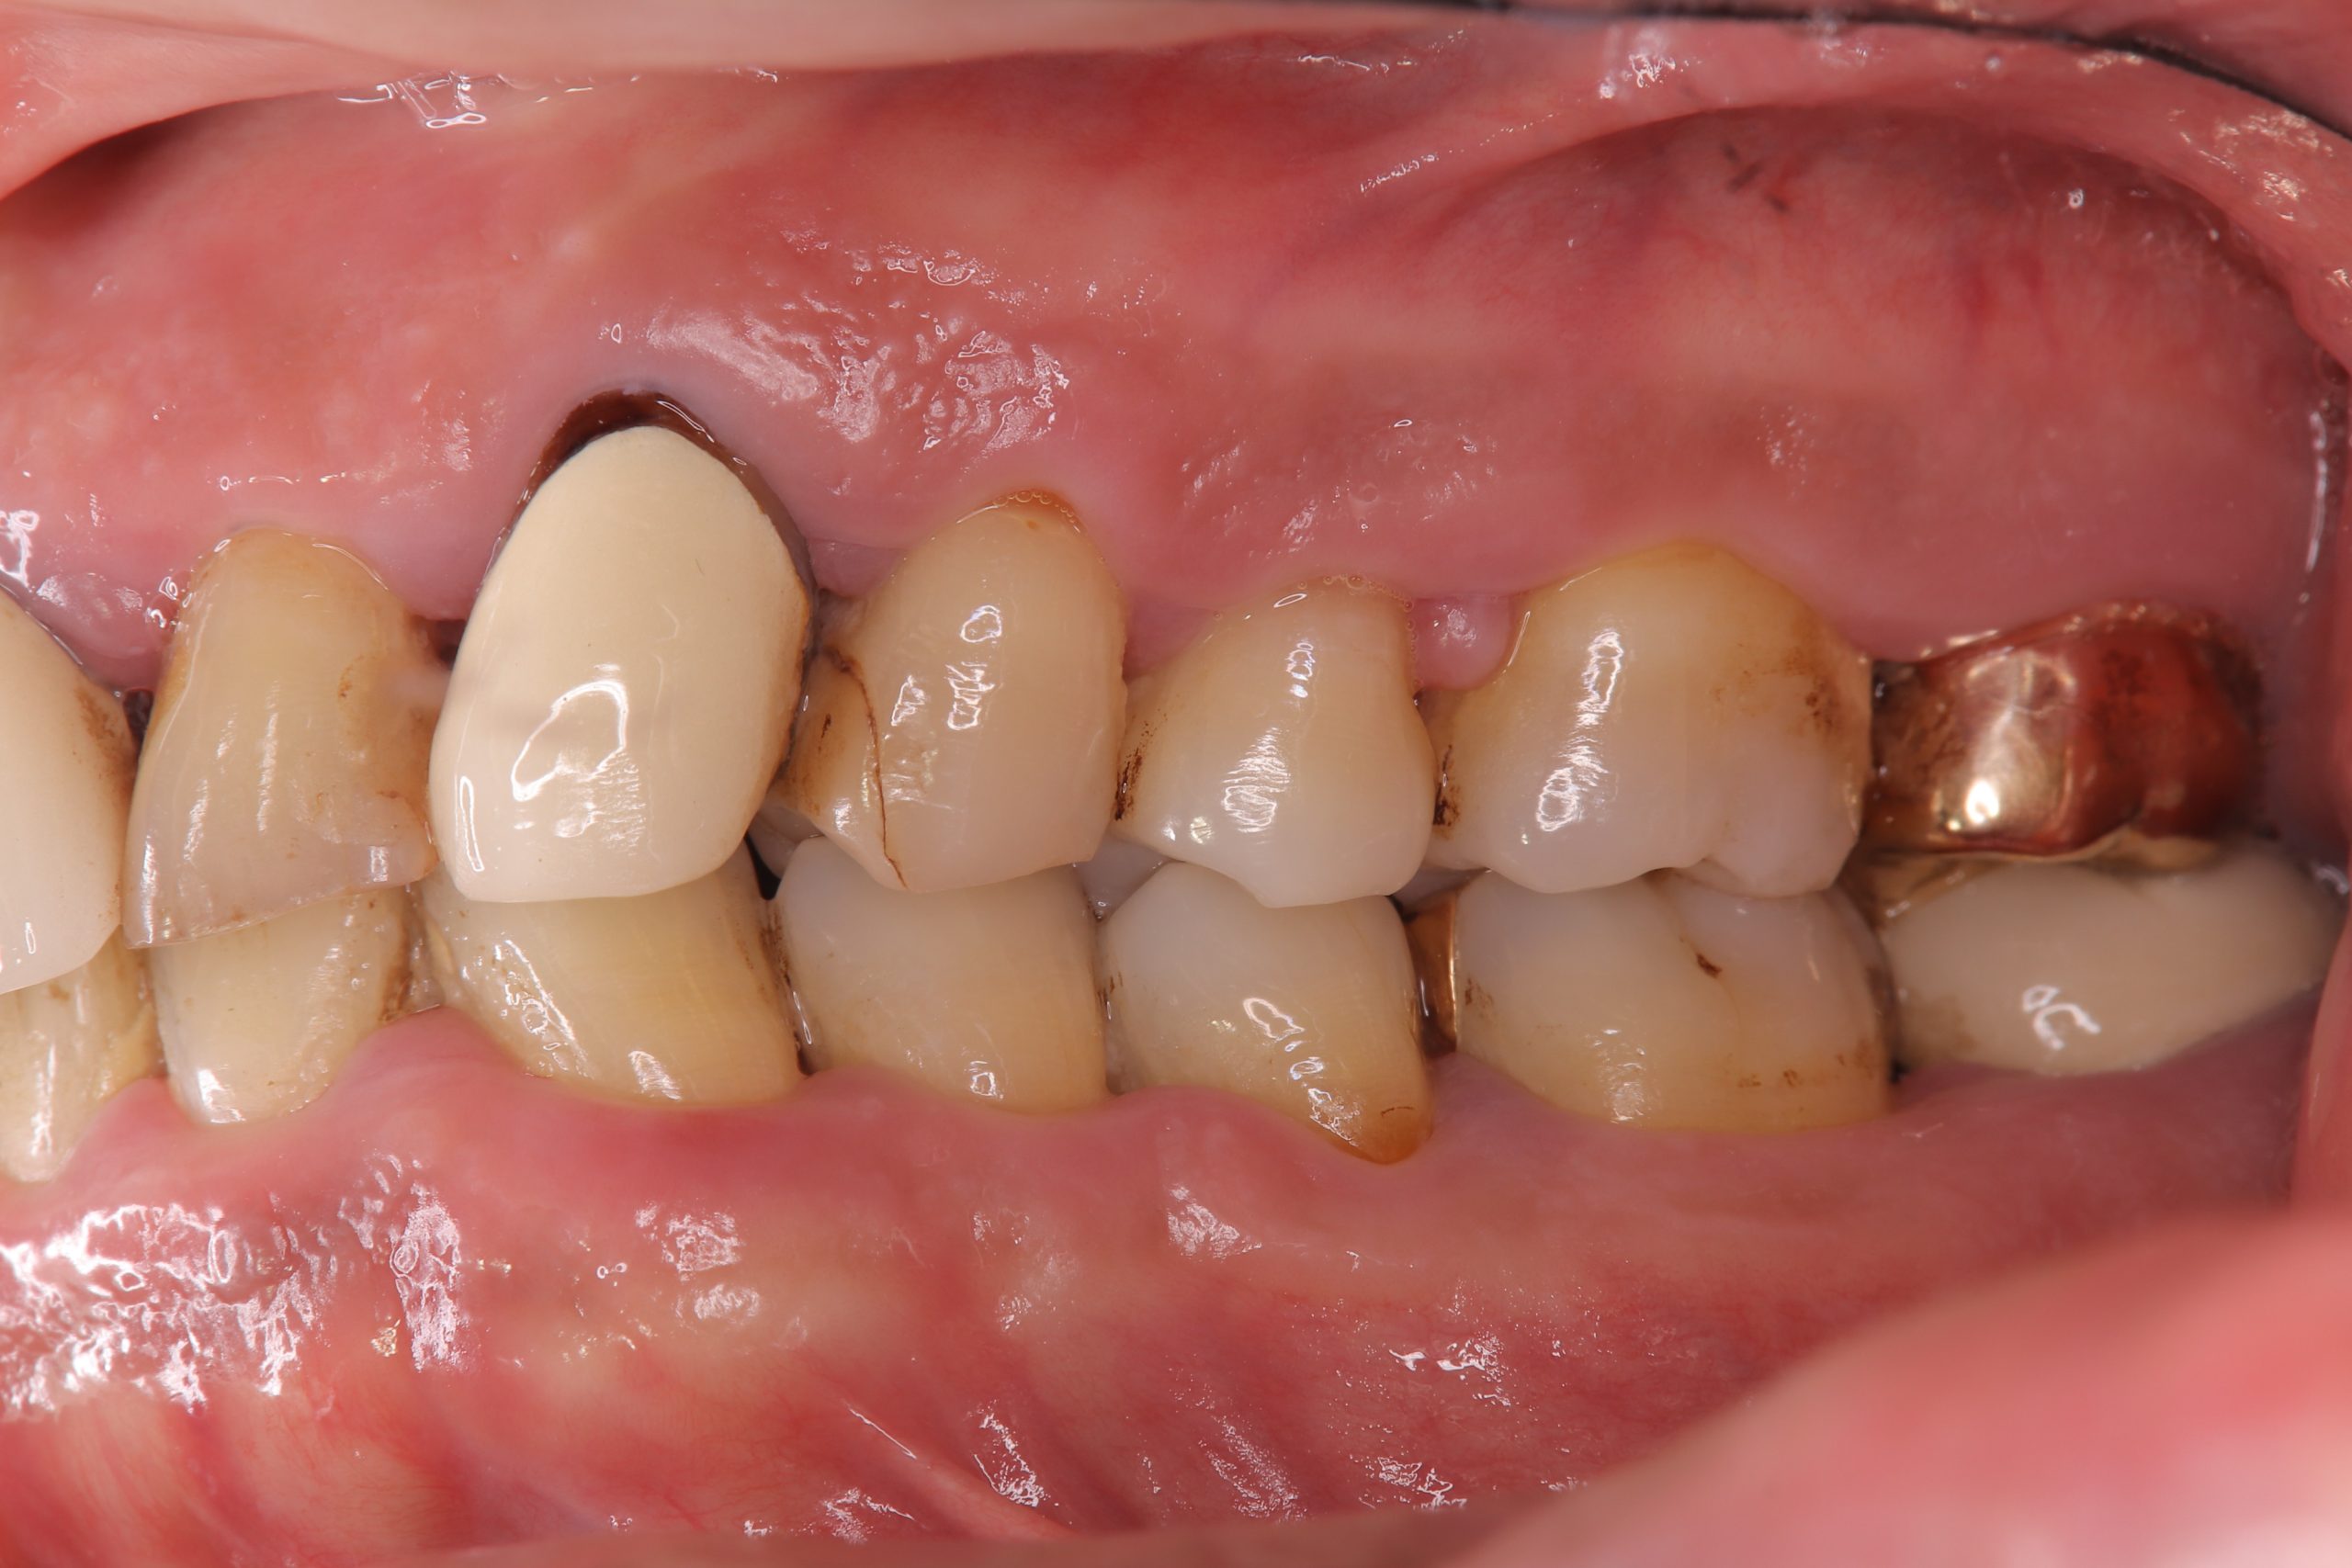

写真は、全体的に歯周病が進行している患者さんのものです。全体的に歯肉が腫れています。

下の第2大臼歯(写真では一番右端)は、ポケットの最深部が12mmもあり、